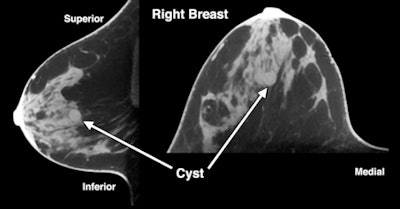

There was size agreement between conebeam CT and mammography in 60% of the findings that were detectable by both systems and for which size information was available. Agreement between mammography and conebeam breast CT for the location of findings was 70%. As for image conspicuity, conebeam breast CT performed better than mammography, which the authors attributed to the breast tissue not being compressed.

| Images are of a 47-year-old woman with a sonographically proven 0.8-cm benign cyst. Above: Mediolateral oblique (left) and craniocaudal (right) digital mammograms do not clearly show a benign cyst. Below: Sagittal and transverse conebeam breast CT images corresponding to the images above show a benign cyst differentiated from surrounding breast parenchyma owing to lack of structure overlap. Images courtesy of the American Roentgen Ray Society. |